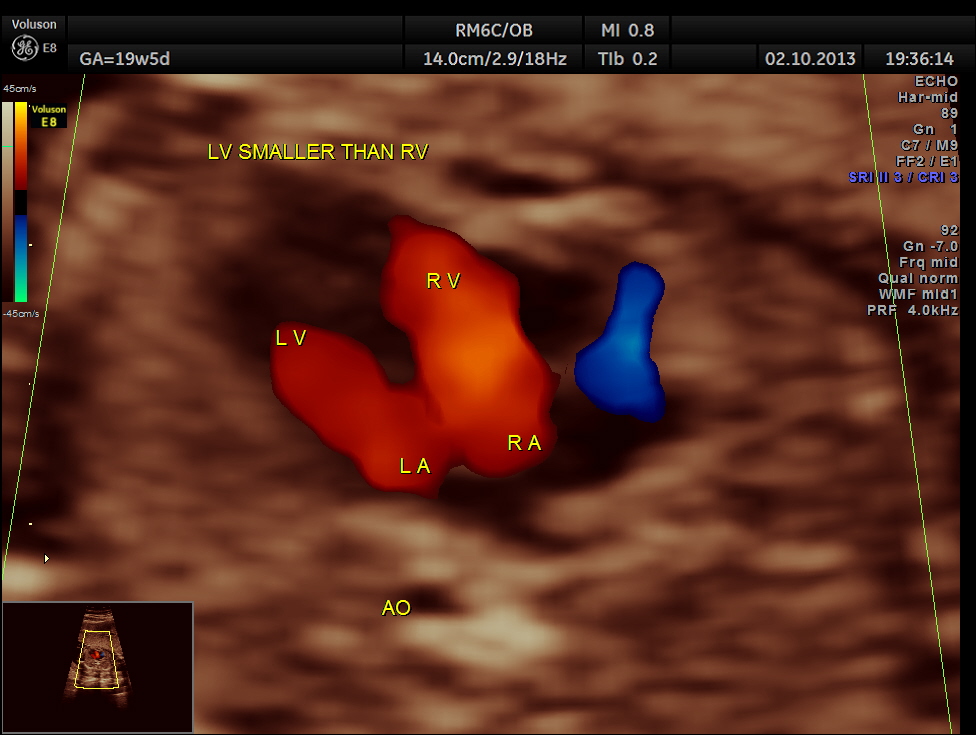

The 4 chamber view is abnormal – LV is smaller than RV.

The following pictures show that the left ventricle appears smaller than the right ventricle. The situs is normal.

Colour flow also rules out the possibility of hypoplastic left heart syndrome.

The diagnosis offered was PROBABLE CO-ARCTATION OF AORTA .